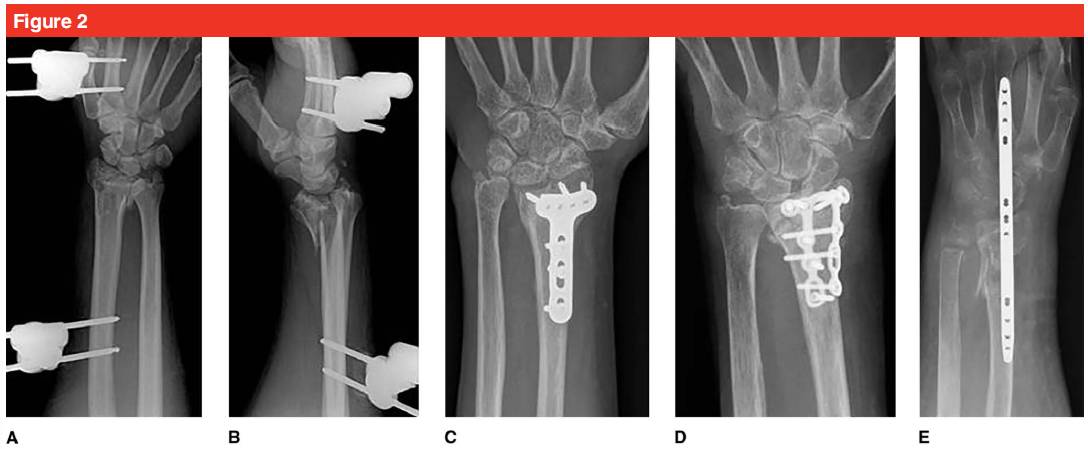

Les options de traitement chirurgical pour les patients âgés présentant des fractures du radius distal comprennent : la réduction fermée et la fixation externe, la fixation percutanée au fil de Kirschner, la réduction ouverte, la fixation par plaque de verrouillage palmaire/dorsale et la fixation par plaque de pont dorsale (voir la figure 2).

L'autre type de réduction ouverte et de fixation par plaque dorsale est principalement utilisé pour le traitement des fractures intra-articulaires.Il peut réduire la surface articulaire sous vision directe sans décaper le tissu ligamentaire du côté palmaire de l'articulation du poignet, réduisant ainsi le risque d'instabilité ultérieure de l'articulation radiocarpienne.Si une fracture du lunatum palmaire est impliquée, elle doit être immobilisée.Pour les patients présentant une fracture de la diaphyse radiale ou des blessures multiples, la plaque de traction intégrée peut être utilisée pour obtenir une réduction par restauration ligamentaire.En même temps, la plaque de traction convient également à la réduction et à la fixation des fractures comminutives et ostéoporotiques du radius distal.La plaque a été retirée 12 semaines après l'opération et un bon effet thérapeutique clinique a pu être obtenu.

La plaque de verrouillage palmaire peut améliorer le raccourcissement radial et l'inclinaison palmaire, et l'incidence des complications est faible.Par rapport à la plaque dorsale, la force de préhension du membre affecté peut être considérablement améliorée dans les 6 mois suivant la chirurgie, et la fonction et la douleur peuvent être améliorées.Des complications telles qu'un re-déplacement de la fixation de la plaque dorsale et une irritation du tendon de l'extenseur des orteils surviennent dans jusqu'à 30 % des cas.Et l'effet de fixation de la plaque palmaire est également meilleur que celui de la broche de Kirschner ou du fixateur externe.